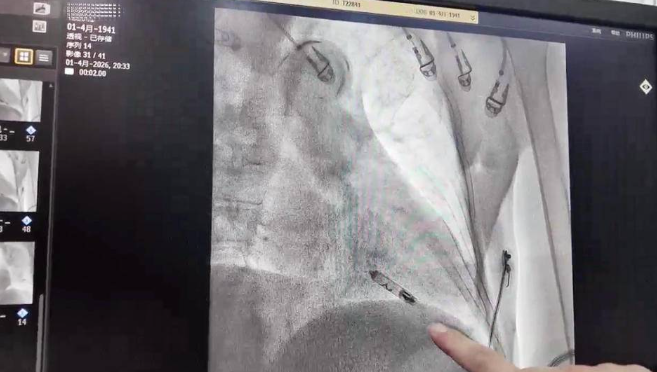

该起搏器体积如胶囊,重不足2克,无需开胸和切口,仅通过股静脉微小针孔即可植入心脏。

手术由心内科团队精准操作,数十分钟完成,起搏参数正常。术后老人恢复迅速,无并发症,次日即可下地活动,平安出院返回医康养中心,实现了微创救治、快速康复与康养的无缝衔接,体现了医康养融合守护高龄老人“心”生命。